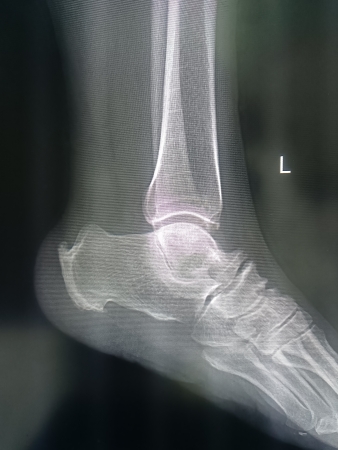

双足踝疼痛病例分享!